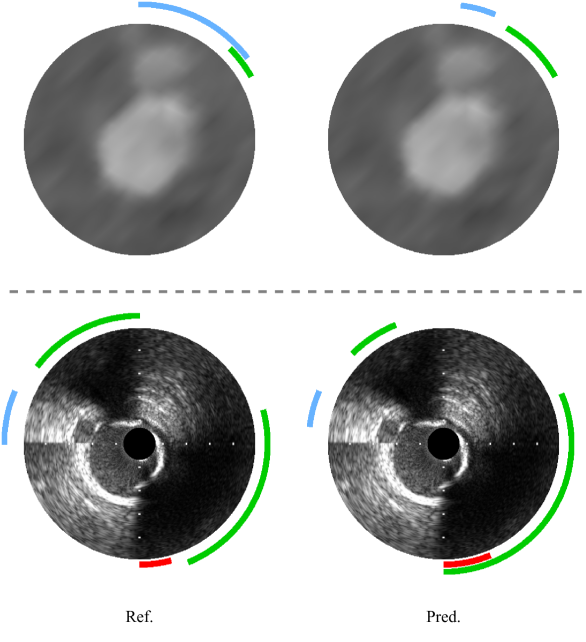

Refer to caption

Figure 5: Examples of classification performance. The top row shows MPR reference annotations (left) and corresponding predictions (right), while the bottom row presents IVUS data in the same format. In both modalities, blue regions denote bifurcations, green regions indicate calcifications, and for IVUS data, red annotations mark guidewire artifacts. While the predictions successfully identify all anatomical landmarks, discrepancies between reference and predictions arise from small differences in angular extent of the annotations, rather than missing or falsely detected structures.

5.1 Classification performance

The classification performance for anatomical features in both IVUS and MPR data is presented in Table 1. For IVUS data, guidewire artifact detection achieved the highest performance with macro-averaged F1 score of 0.977, followed by calcifications (0.781) and bifurcations (0.687). The detection of these features in MPR data showed similar trends, with calcifications and bifurcations achieving macro-averaged F1 scores of 0.740 and 0.724, respectively. As expected for features that typically span multiple angular positions within a frame, macro-averaged metrics computed at the frame level consistently outperformed their micro-averaged counterparts that treated each angular prediction independently. Qualitative examples of the classification performance for both modalities are shown in Fig. 5.